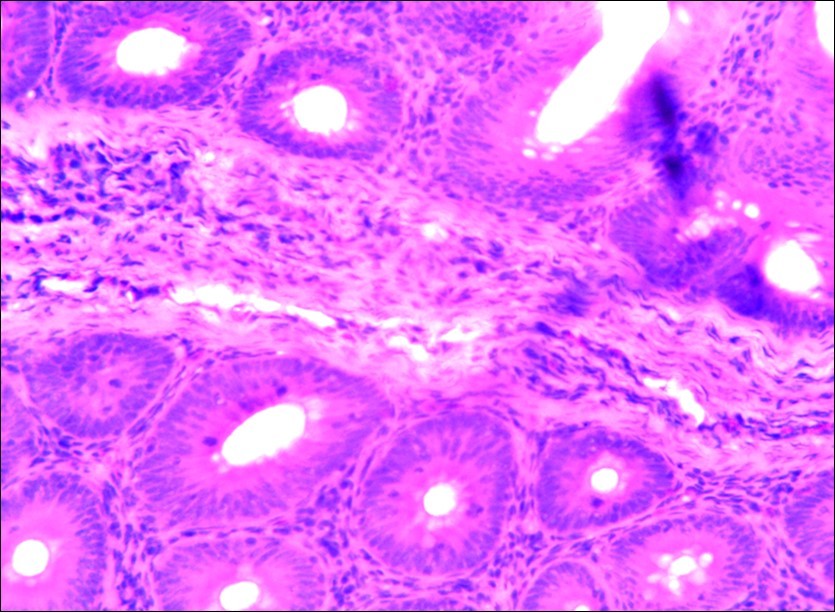

Figure 3.Photomicrograph of caecum of chick uninfected and untreated showing no observable lesion X250 (H&E).

In this study, the reduction in oocyst count observed in the treated group was compared with amprolium could be attributed to the presence of a bioactive compounds azadiractin A which is known to bind membrane cholesterol, altering the integrity of the parasite membrane, resulting in loss of homeostasis and eventual death of the parasite 29]. Also, limonoids contained in NeemAzal® inhibit protein digestion and uptake of vitamins and minerals by the parasites in the gut 17. This action results in impaired nutrient utilization, reduced growth, and multiplication of the parasite which could contribute to the reduced oocyst count observed. Extracts of neem and mahogany when used individually have been reported to reduce oocyst count in avian coccidiosis 11,12. The observed reduction in oocyst count and the significant increase in weight gain of the birds when treated with NeemAzal®, as compared with the negative control group could probably be due to the inhibition of inflammation in the intestinal mucosa which is suggestive of an increased nutrient absorption across the intestinal wall and enhanced feed conversion ratio compared to the negative control this is in agreement with reports by Nwosu et al.12 and Biu et al.11 who also reported an increased weight gain and feed conversion ratio in birds treated with only Khaya senegalensis extracts and Azardiractaindica, respectively. The observed increase in RBC and haemoglobin concentration is indicative of the erythropoieticability of the NeemAzal®, which is beneficial since the Eimeria parasite in the epithelia of the intestines causes bloody diarrhoea and consequently anaemia (Table 1). This finding is in consonance with 15 who reported an anti-anaemic effect of Khaya Senegalensis on phenyl hydrazine-induced anaemia in rats. Neem has been shown to possess anti-anaemic properties in rats 14. The significant increase in mean weight gain in treated birds when compared to the negative control is possibly due to the inhibition of inflammation in the intestinal mucosa which is suggestive of an increased nutrient absorption across the intestinal wall and enhanced feed conversion ratio compared to the negative control. Nwosu et al.12 and Biu et al.11 reported an increased weight gain and feed conversion ratio in birds treated with only Khaya Senegalensis andAzadiractaindica extracts, respectively. In a similar study, Neem acts like toltrazuril exhibiting anticoccidial. In addition, exposure of broiler chickens to 20000 Oocysts of Eimeria tenellacaused generalized degeneration of the caecal glands with massive Oocysts and gametocyts within the caecal glands with fibrosis (Figure 3, Figure 4 & Figure 5), however, broiler chickens treated with NeemAzal® post exposure to 20000 Oocysts of Eimeria tenella, shows equal numbers of caecal tissues with non-observable histopathological lesions (Figure 4), possibly due to the antioxidant and anti-coccidian effects of NeemAzal®. The exact mechanism of action of neem against coccidian parasites is unknown, but a report by the National Research Council 1992 30, suggested that aqueous neem leaf extract, when taken orally, produces an increase in red cells, white blood cells and lymphocyte counts thus enhancing the cellular immune response, increasing antibody production and so most pathogens can be removed before they cause the symptoms associated with disease this was in agreement with this study as seen in Table a remarkable increase of the RBCs.